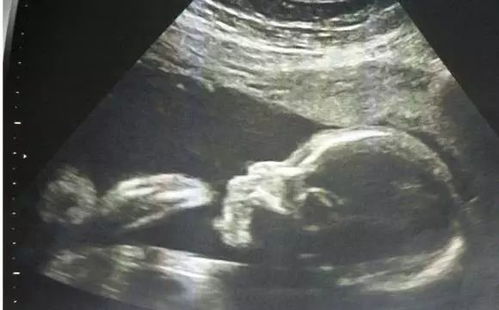

24周是孕期的一个重要阶段,此时胎儿已经发育到一定程度,器官结构逐渐完善,系统B超可以更全面地评估胎儿的生长发育情况。通过系统B超,医生可以观察胎儿的各个器官、四肢、头部等部位,及时发现潜在的问题。

系统B超是孕期24周的重要检查项目,通过系统B超可以全面了解胎儿的生长发育情况,及时发现潜在问题。孕妇应重视系统B超检查,按照医生的建议进行预约和检查,确保胎儿的健康发育。